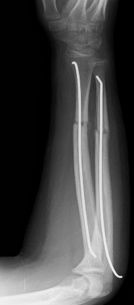

Las fracturas de ambos huesos del antebrazo al mismo nivel, con líneas de fractura oblicua-transversa o desplazamiento convergente son inestables y precisarán de tratamiento quirúrgico. En estos casos está indicado, dependiendo de la edad del paciente, el tratamiento mediante reducción y osteosíntesis. El enclavado intramedular elástico es el tratamiento de elección (Figura 15).

Figura 15: a-Imagen clínica de fractura de antebrazo derecho con gran deformidad. b- Radiografía donde se aprecia fractura de radio-cúbito de trazo transverso en el mismo nivel. c, d-Enclavado intramedular elástico. e,f- Imagen final con buena consolidación ósea.